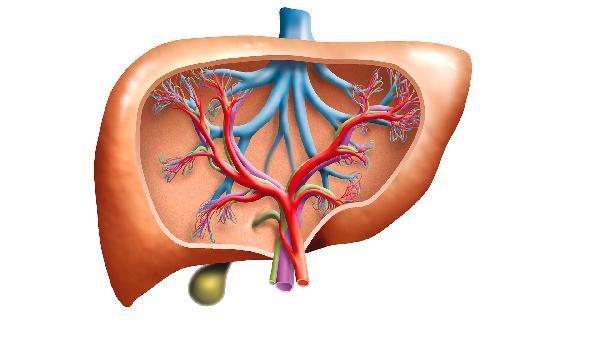

肝占位性病變是一種影像學上的描述,主要是肝臟影像學中的異常信號區(qū)域。肝占位性病變可能是良性病變或惡性腫瘤;可能是原發(fā)性病變,也可能是轉移性病變。常見的良性疾病包括肝囊腫、肝血管瘤、肝腺瘤、肝局灶性結節(jié)樣增生。惡性腫瘤主要是肝癌,可分為原發(fā)性肝癌和轉移性癌。原發(fā)性肝癌包括肝細胞型肝癌、膽管細胞型肝癌和兩者的混合型。轉移性肝癌主要是由肝轉移引起的其他病變,更常見的是結直腸腫瘤。肝占位需要通過加強CT或磁共振和腫瘤標志物來進一步判斷良惡性,必要時還可以在影像學的指導下進行穿刺活檢。